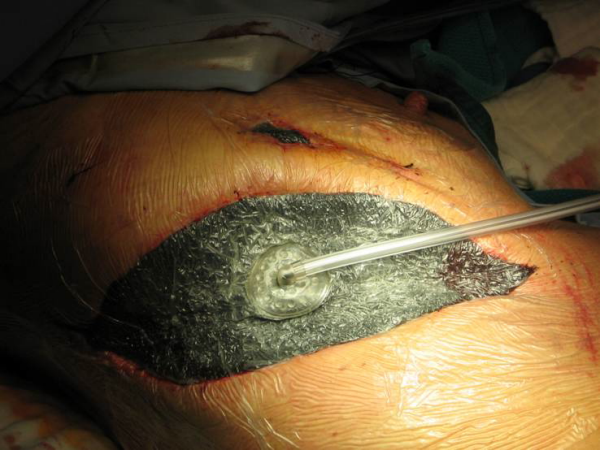

Für das Infektionsmanagement verwenden wir bevorzugt zum Wundverschluss Polyurethanschwämme, welche mit einem Sog von 125 mm Hg an das Sternum gepresst werden (Abbildung 18 [Abb. 18]). Durch diese Vakuumtherapie (VAC®) führen wir zwar eine „offene“ Behandlung durch, aber in einem „geschlossenen“ System. Für den Patienten ist diese Methode von hygienischer Seite wesentlich vorteilhafter, da eine raschere Wundreinigung mir signifikanter Keimreduktion wegen der sofortigen Sekretabsaugung erfolgt, ohne Gefahr einer zusätzlichen Bakterienbesiedlung. Die Wunde ist leichter zu pflegen (weniger Verbands wechsel) und wegen der Geruchsneutralität bedeutet dies für den Betroffenen auch eine gesteigerte Lebensqualität.

Des Weiteren wird die Granulation angeregt sowie die Wundheilung beschleunigt. Bei Sternuminstabilität bzw. -dehiszenz bewirkt das „VAC®“ eine Reduktion der Scherkräfte, wodurch sich der knöcherne Thorax rascher stabilisiert. Auf diese Weise verbessert sich auch signifikant die Lungenfunktion und führt zu einer Senkung der pulmonalen Komplikationen. Bei freiliegenden intrathorakalen Organen (Herz, Lunge) sollte diese mit einem Silikonnetz (Mepithel®) abgedeckt werden, um einen direkten Kontakt mit den Polyurethanschwämmen zu verhindern, um zum Beispiel keine Gefäßarrosion zu provozieren.

Die durchschnittliche VAC-Dauer beträgt 10 Tage mit einem zweitäglichen Wechsel der Schwämme. Sind saubere Wundverhältnisse erreicht, kann auch eine Re-Cerclage erfolgen. Bei einer Osteomyelitis wird ein Muskellappen interponiert, etwa der M. pectoralis oder der M. rectus abdominis bei Befall des unteren Sternumdrittels. Bei unbrauchbaren Muskeln lässt sich auch das Omentum majus verwenden, das besonders bei tiefen und irreguären Defekten sich als „Füllmaterial“ besonders gut eignet. Manche Autoren verwenden nach Debridement der Nekrosen und Wundsäuberung primär Muskellappenplastiken; eine primär plastische Deckung birgt aber die Gefahr, dass noch infizierte Nekrosen zurückbleiben und zu einem Infektionsrezidiv führen, eventuell sogar zu einer Sepsis. Der Einsatz der Vakuumtherapie ist daher besser zur Vorbereitung einer definitiven Muskel- oder Omentumplastik geeignet und dient als „Bindeglied“ zwischen Debridement und plastischer Deckung.